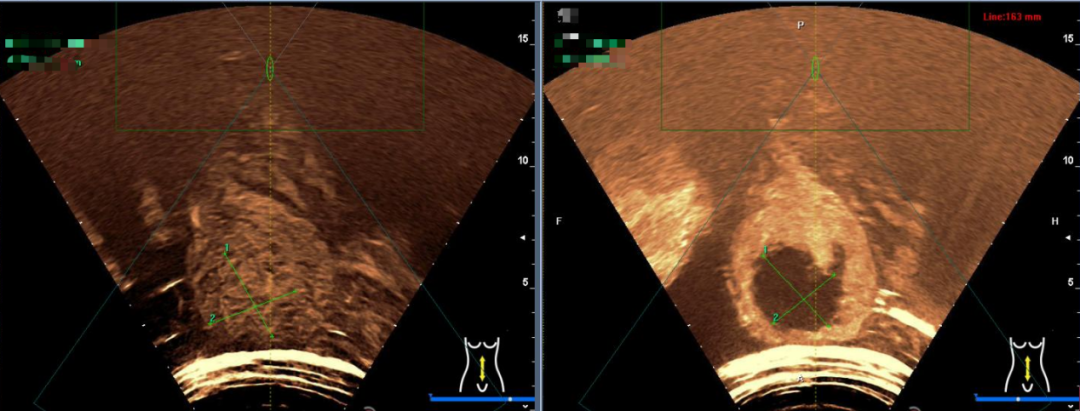

张家港市第一人民医院海扶微无创治疗中心积极响应本次公益活动,与全球200多家中心一起全程线上参与,当日使用海扶设备顺利完成1例子宫腺肌瘤患者的高强度聚焦超声消融手术。术中患者耐受良好,成功实现了保子宫的愿望,同时切实为患者的减轻了经济负担。术后当天,患者反应良好,并于术后第二天顺利出院。

△术后造影对比